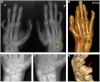

The study of homeotic-transformation mutants in model organisms such as Drosophila revolutionized the field of developmental biology, but how these mutants relate to human developmental defects remains to be elucidated. Here, we show that Liebenberg syndrome, an autosomal-dominant upper-limb malformation, shows features of a homeotic limb transformation in which the arms have acquired morphological characteristics of a leg. Using high-resolution array comparative genomic hybridization and paired-end whole-genome sequencing, we identified two deletions and a translocation 5' of PITX1. The structural changes are likely to remove active PITX1 forelimb suppressor and/or insulator elements and thereby move active enhancer elements in the vicinity of the PITX1 regulatory landscape VSports手机版. We generated transgenic mice in which PITX1 was misexpressed under the control of a nearby enhancer and were able to recapitulate the Liebenberg phenotype. .